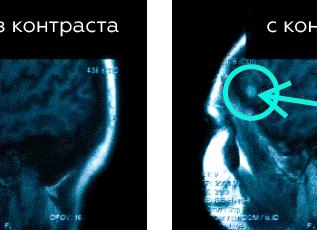

Визуализировать органы шеи и мягкие ткани очень сложно на рентгене, для этого применяются контрасты, да и то диагноз выставляют косвенно. Революционным открытием в этом направлении стало МРТ (магнитно-резонансная томография), она позволяет увидеть патологию мягких тканей. У человека в области шеи, головы есть много органов, сосудов, нервов, которые необходимо визуализировать, чтобы установить точный диагноз. Проведенное МРТ шейного отдела, головы позволяет это сделать наиболее качественно и оптимально.